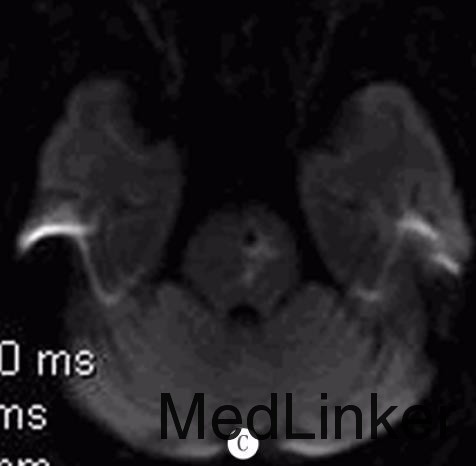

入院查体:BP158/98mmHg,神志清,构音障碍,双瞳孔等大等圆,对光反应灵敏,双眼各向活动充分,未见眼震,示齿口角不偏,伸舌居中,四肢肌张力正常,右下肢肌力4级,余肢体肌力正常,双侧病理征阴性,双侧感觉对称,颈软。急行颅脑CT 检查示:双侧侧脑室周围多发片状低密度影。颅脑MRI检查(距发病30余小时)示:双侧脑实质、脑干多发血管源性脱髓鞘,双侧基底核区多发脑软化灶,DWI序列可见脑桥偏左侧一圆形低密度灶,灶周稍高信号;SWI证实脑桥偏左侧及双侧基底核区多发顺磁性物质沉积。颅脑MRA检查示:颅内动脉粥样硬化改变。颈部血管超声检查示:双侧颈总动脉、左侧颈内动脉粥样硬化斑块(易损斑块)形成。

诊断:脑微出血?给予阿司匹林抗血小板聚集、阿托伐他汀稳定斑块、改善循环及对症支持治疗,病人右下肢无力稍缓解。5d后病人右下肢无力较前加重,查体示右侧肢体肌力3级,复查颅脑MRI示:脑桥偏左侧脑梗死。加用氯吡格雷抗血小板治疗,病人症状渐好转,病情平稳后给予降压治疗,出院时仍言语欠清,右侧肢体无力较前好转。

脑微出血(CMB)反映脑小血管疾病的出血倾向,是高血压性小血管病和脑淀粉样血管病的影像学标志,多被认为是无症状性的,缺乏急性临床表现。但WATANEBE等报道1例在中脑急性形成的CMB导致核上性眼肌麻痹,认为单个CMB在功能区急性形成也可能引发临床表现。此外,脑淀粉样血管病和高血压病人出现短暂性神经功能障碍也可能与CMB有关。该例病人首次出现右下肢无力时颅脑CT及MRI检查均未见明显责任病灶,但DWI序列可见脑桥偏左侧一圆形低密度灶,后经SWI检查证实为CMB。病人既往有高血压史,急性起病,脑内可见多发白质病变、腔隙性梗死等脑小血管病标志,但均非急性形成,在运动传导通路上可解释临床症状的仅有脑桥左侧CMB。由此推测其首次无力原因可能为脑桥单发CMB,此CMB与基底核区CMB影像学表现的不同可能反映了这两类CMB发生机制及病理学表现的差异,其病灶边缘呈环形DWI高信号也支持此CMB为急性形成。提示少数临床疑诊急性脑血管病的病人可能由急性CMB形成引起,对CMB的检测可能有助于诊断和鉴别诊断。但由于该病人发病前未行CMB检测,该单发CMB是否为急性形成尚不能肯定。DOI:10.13361/j.qdyxy.201502039